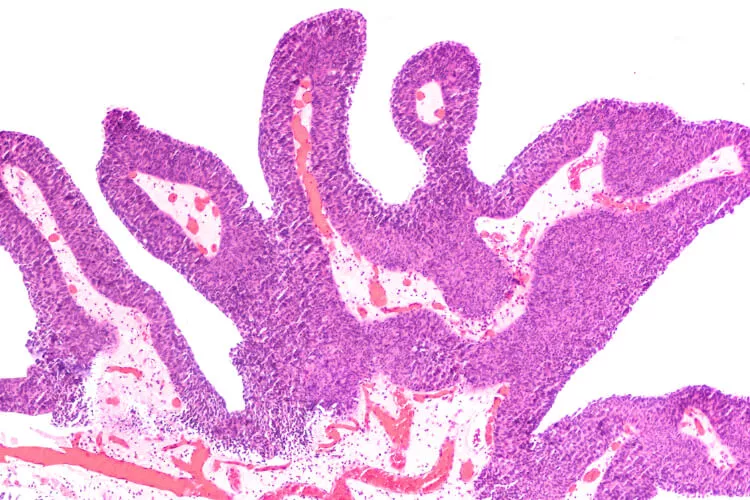

Živou debatu v sekci Rapid-fire odstartoval prof. MUDr. Marek Babjuk, CSc., prezentací kazuistiky fragilního 86letého pacienta (celoživotního kuřáka) s několika komorbiditami (včetně kardiovaskulárních), u nějž již v roce 2019 na jeho pracovišti po zjištění 5 papilárních tumorů (velikosti 4–10 mm) nízkorizikové klasifikace Ta LG/G1 (uroteliální karcinom) provedli jejich transuretrální resekci (TURBT) a instilaci mitomycinem C, a kterého opětovně přijali po 7 měsících poté, co u něj cystoskopie odhalila 6mm papilární lézi v zadní stěně močového měchýře a obdobný 5mm nádor na jeho levé straně. Poté M. Babjuk oslovil sledující experty z předních světových urologických pracovišť, aby se vyjádřili k terapeutickým možnostem u takového případu. Přiklonit se k standardnímu řešení (TURBT a intravezikální léčba), nebo ke konzervativnějšímu přístupu s aktivním sledováním nádoru a fulgurací?

Možnost vyjádřit se přes webkameru a mikrofon dostává prof. Wassim Kassouf z McGill University v Kanadě – ten odkazuje na známá a publikovaná fakta (Matulay JT et al., BJU Int 2020; Kim JK et al., J Cancer 2017; Oliver K, Bosset JF, Urol Oncol 2015; Herr HW et al., J Urol 2007), a sice, že až 60 % karcinomu močového měchýře je nízkorizikových (LG Ta) s rekurencí ve 30–60 % případů, avšak dobrou prognózou (velmi nízké riziko progrese – 3 % do 10 let a nádorově specifická mortalita < 1 %). Dle jeho názoru tak jde o malignity, které by nemusely být až tak velkou zátěží pro zdravotnický systém a společnost – terapie by u nich nemusela být až tak intenzivní (bez zhoršení parametrů přežití pacientů), jak se ostatně děje i u nízkorizikových karcinomů prostaty či malých nádorových lézí na ledvinách (SRM). A obrací pozornost kolegů ve studiu i u obrazovek všude po světě mimo jiné na práci autorů Herr HW et al., (J Urol 2002), která ukazuje, že urologové dovedou u nízkorizikových karcinomů močového měchýře velmi přesně predikovat rizikovost rekurentní malignity – v citované práci bylo cytoskopickou analýzou 144 rekurentních papilárních tumorů správně klasifikováno jako TaLG až 99 % lézí. Obdobně tomu bylo v novější (prospektivní) studii (Mariappan P et al., Urology 2017) – v ní byla predikce nízkorizikového nádoru u 248 subjektů správná v 88 % případů (a až u 88 % analýz, pokud se v potaz braly jen léze menších rozměrů). W. Kassouf též zmiňuje, že ačkoliv se TURBT obecně považuje za menší a poměrně bezpečný výkon, jsou zaznamenávány komplikace při cca 5 % zákroků (Collado A et al., J Urol 2020), jako například perforace, krvácení, opakované hospitalizace, reoperace a jiné dopady na kvalitu života pacientů (nehovoře o nákladech), což jistě není možné podceňovat, speciálně u starších a křehčích nemocných. Data autorů Pereira JF et al. (Urology 2019) po analýze > 24 000 pacientů po TURBT tyto počty potvrzují (vč. 0,8% mortality). W. Kassouf poté obrací pozornost sledujících odborníků k datům o využití ambulantní fulgurace (menších povrchových nádorů) – Donat SM et al. (J Urol 2004) hlásili po prospektivním sledování (střední délky 2,6 roku) u 267 pacientů dobrou efektivitu tohoto výkonu: podobné výsledky nádorově specifického přežití, míry progrese i rekurence (46 %) jako u transuretrální resekce. Dle jeho slov je u menších povrchových lézí také možné využít laserovou ablaci s lokálním znecitlivěním (u ní uvádí 4% rekurenci původního nádoru po dvouletém sledování prospektivní studie 151 subjektů z publikace Syed HA et al., J Endourol 2013). Pouhé aktivní sledování nízkorizikových tumorů prezentovaného typu W. Kassouf obhajuje s odkazem na metaanalýzu týmu Marcq G et al., (Transl Androl Urol 2019) a novější prospektivní data dlouhodobého follow-up od autorů Hurle R et al., z publikace v Eur Urol Oncol 2021, která ukazují, že tento šetrný přístup by mělo být možné využít u 40–50 % těchto pacientů. Dle něj by kombinace fulgurace a aktivního sledování mohla omezit negativní vlivy TURBT a anestezie, redukovat počty vyšetření i obavy pacientů a v neposlední řadě snižovat náklady na zdravotní péči.